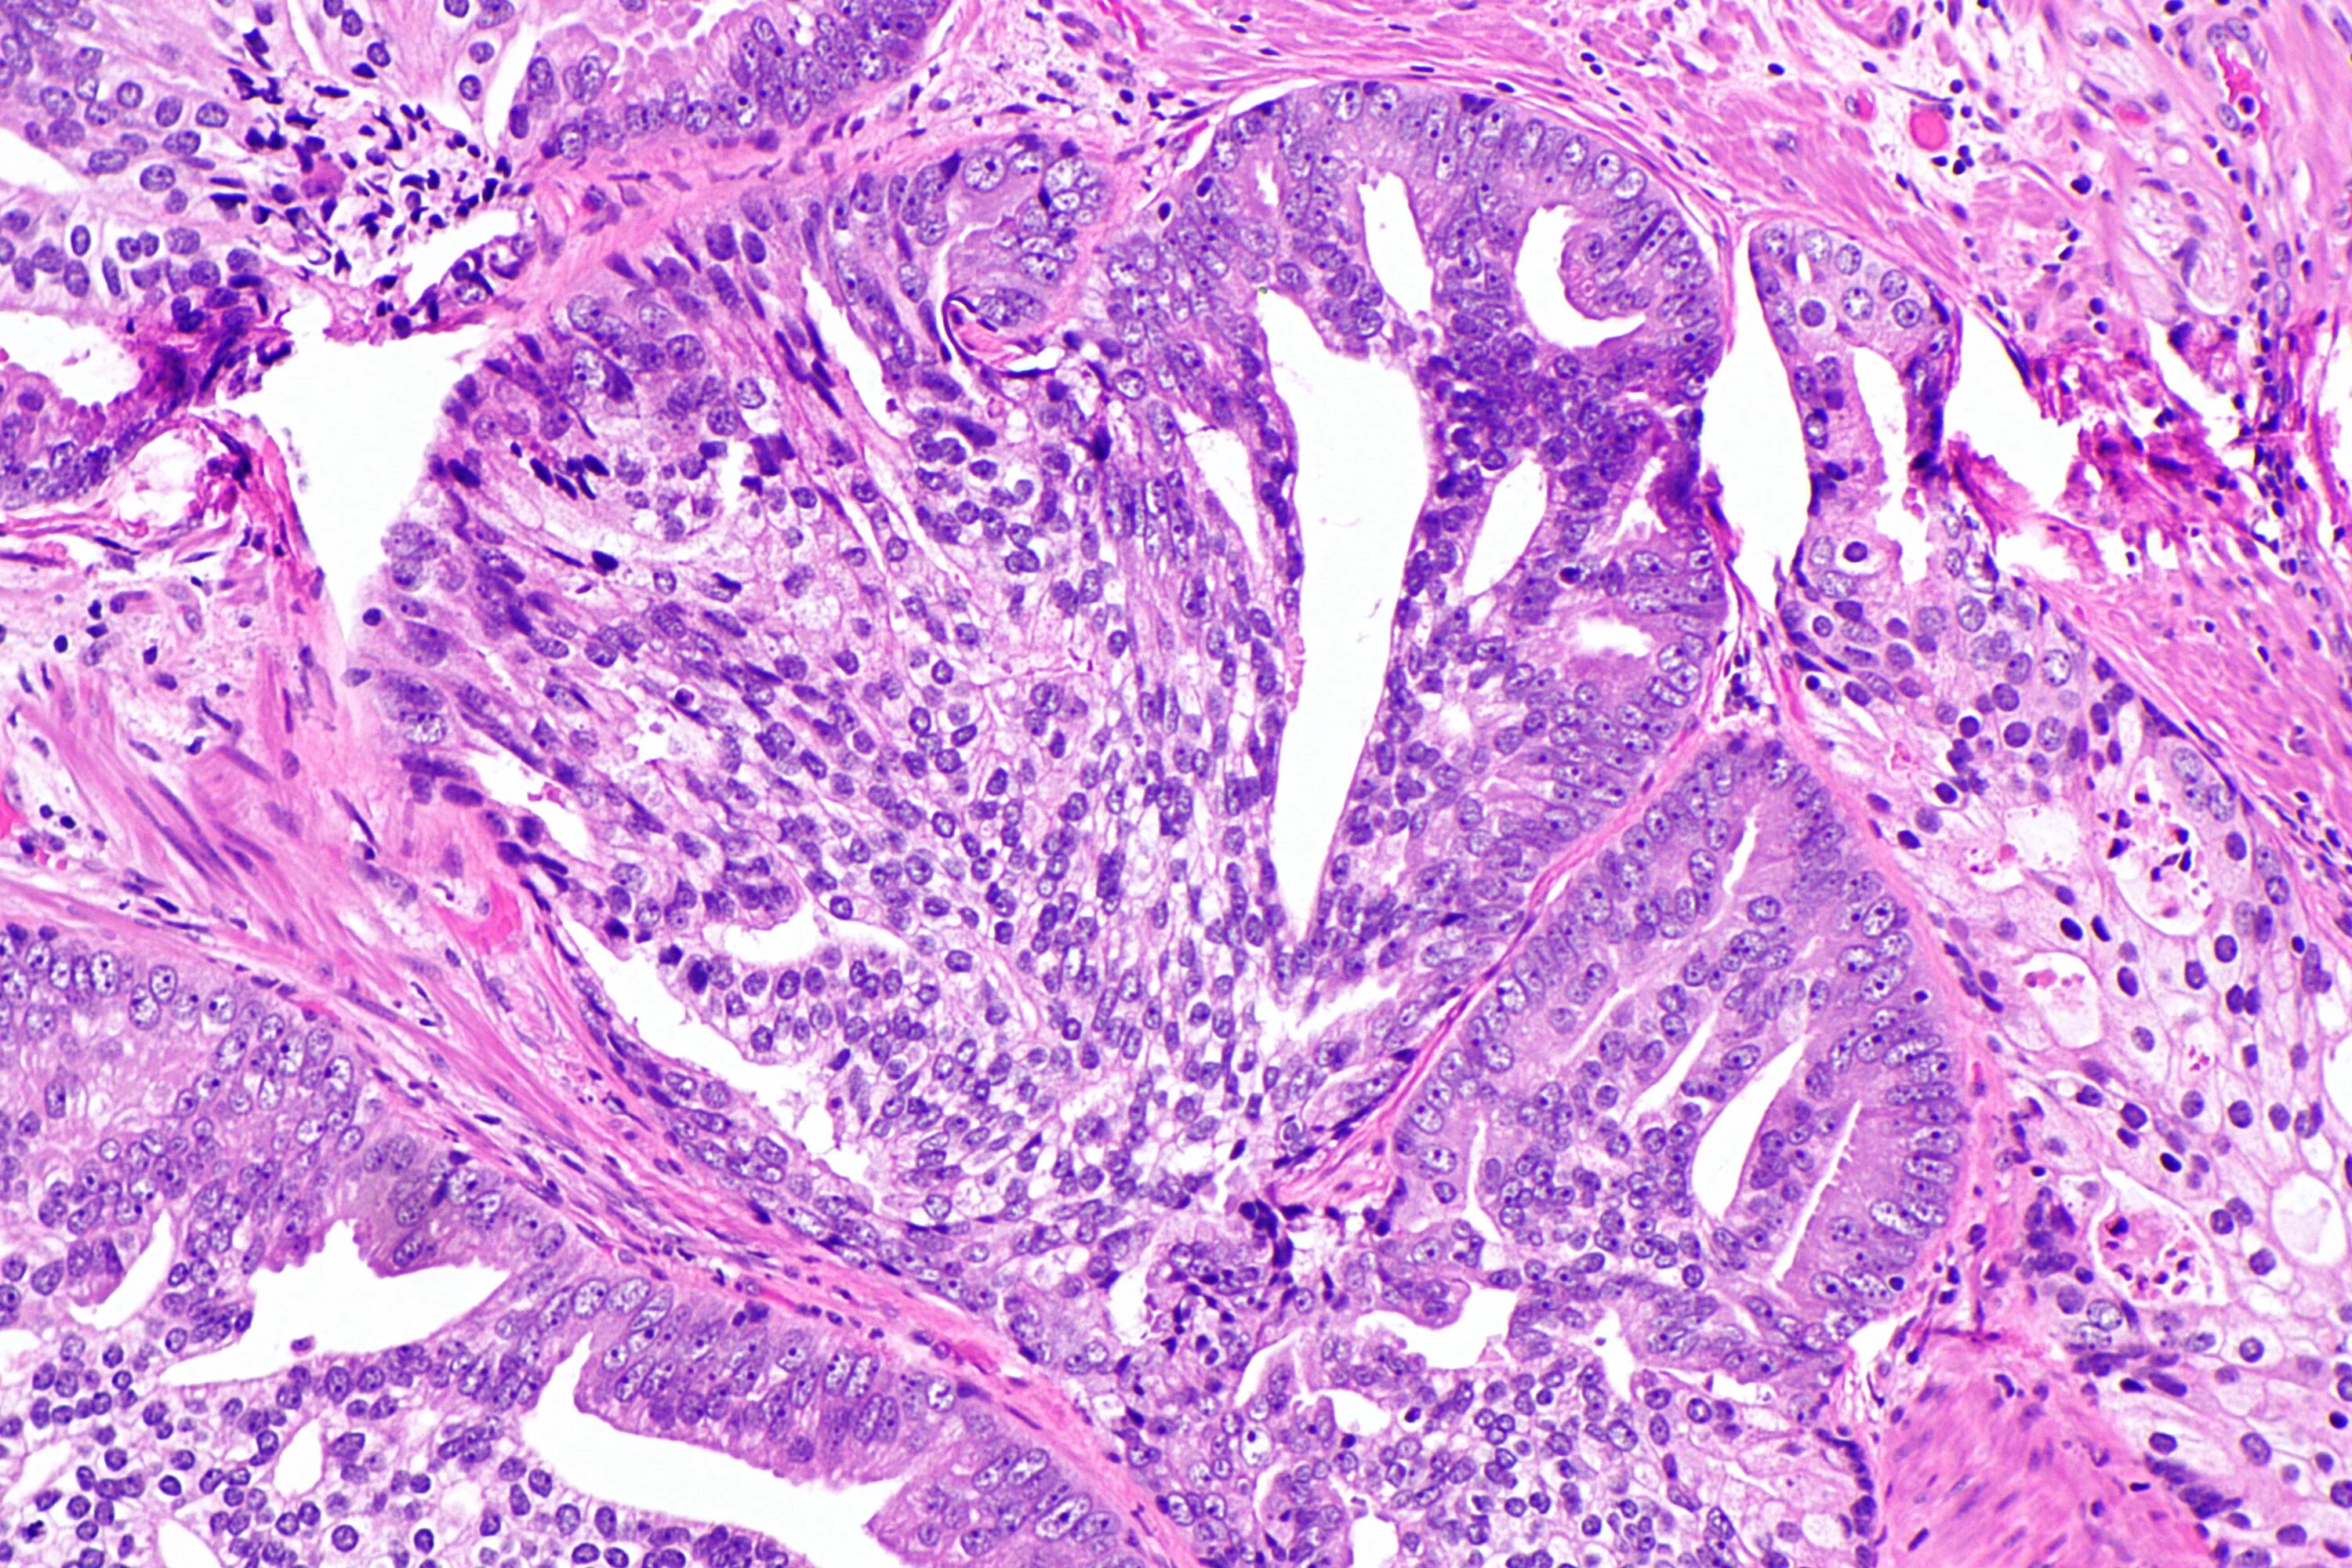

Гистология при раке